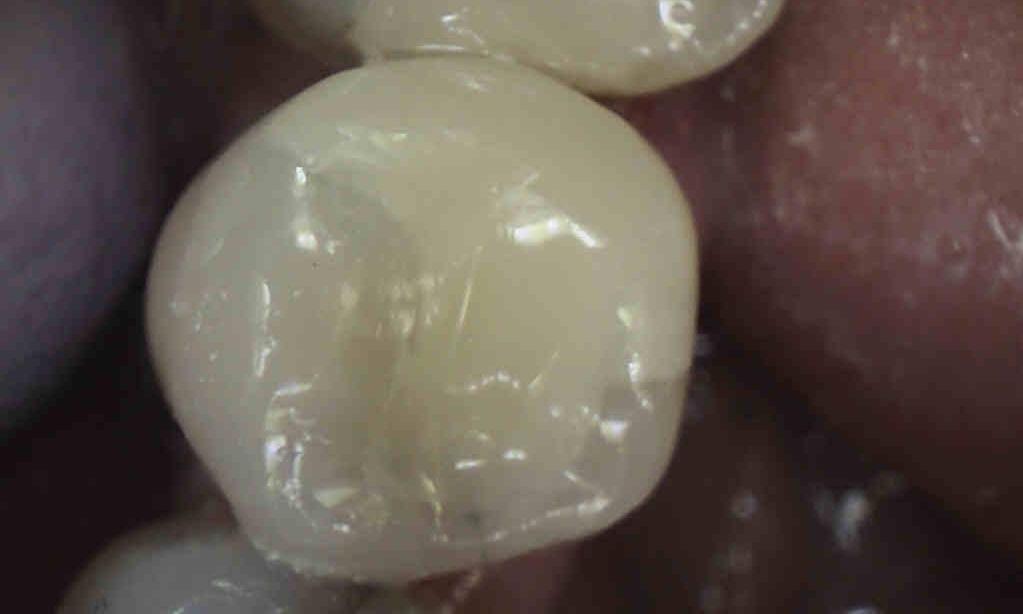

This patient presented to our office with a failing amalgam (silver) filling. After removing the old restoration, we treated the cavity from underneath it. We then placed a more esthetic composite restoration. The patient was thrilled.